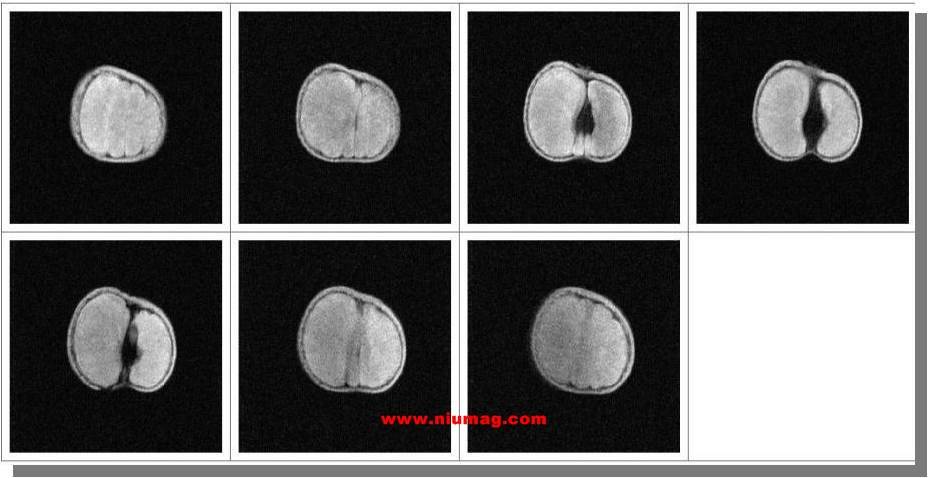

梨核磁共振多層成像圖-失狀位